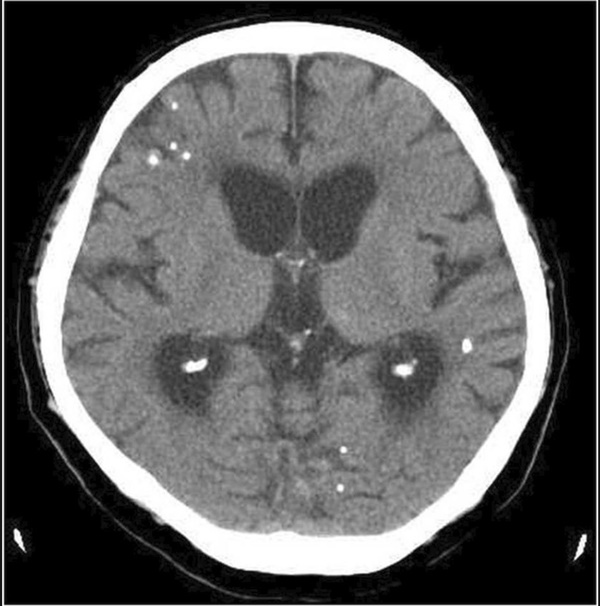

Bác sĩ lập tức chỉ định chụp cộng hưởng từ, chụp cắt lớp vi tính và chụp X-quang cho bệnh nhân. Kết quả, các bác sĩ vô cùng kinh sợ khi phát hiện hàng trăm trứng sán dây nhỏ xíu lúc nhúc trong gần như mọi phần trong cơ thể người bệnh.

Qua hình ảnh chụp chiếu, dễ dàng nhận ra trứng sán dây xuất hiện trong não, cột sống, mông, cổ, ngực và chân cụ ông đã về hưu. Cụ được chẩn đoán mắc bệnh ấu trùng sán lợn. Đây là bệnh nhiễm trùng sán dây, thường là hậu quả của việc ăn thịt lợn bị nhiễm sán.

Tiến sĩ Ming-Pin Lin, một trong các tác giả viết về trường hợp của bệnh nhân 74 tuổi trên, cho biết, hình chụp chiếu thể hiện rõ "một bầu trời đầy sao" ấu trùng sán và còn tiết lộ cả tình trạng vôi hóa của cơ. Tiến sĩ chia sẻ thêm, biện pháp điều trị bao gồm thuốc kháng ký sinh trùng, steroids và đặt thiết bị vào não để giảm áp lực lên não gây ra bởi hiện tượng ứ dịch.

Hình ảnh trứng sán dây ở cột sống thắt lưng và mông, các chấm trắng cho thấy cụm trứng sán dây trong não của bệnh nhân